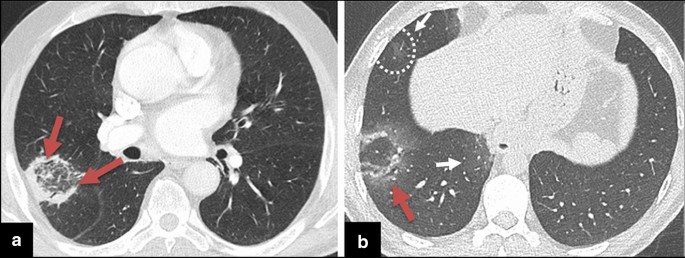

Focal GGOs or opacities with rounded morphology may be encountered in COVID-19 pneumonia [10]. In the presence of focal GGOs, neoplastic processes should also be considered. Preinvasive lesions (atypical adenomatous hyperplasia and adenocarcinoma in situ), early-stage adenocarcinoma (Fig. 7), and multifocal adenocarcinoma (Fig. 8) may have variable imaging features, such as pure GGOs, GGOs in combination with consolidation, nodules surrounded by a halo of GGO (CT halo sign), and GGOs with crazy-paving pattern. Air bronchograms in larger lesions, pleural effusion, and lymphadenopathy can be seen [34,35,36,37]. Similarly, mucinous adenocarcinoma metastases can manifest as focal or multifocal GGOs, consolidations, and nodules with a CT halo sign [38, 39]. Besides tumoral growth, CT halo sign can represent peritumoral hemorrhage in hemorrhagic metastases such as angiosarcoma [17] (Fig. 9).

COVID-19 pneumonia-mimicking adenocarcinoma of the lung. a Axial chest CT image shows a rounded focal opacity histopathologically proven to be adenocarcinoma in the right upper lobe (arrow). b–d CT images of three different COVID-19 patients demonstrating unifocal round opacities mimicking adenocarcinoma (arrows)